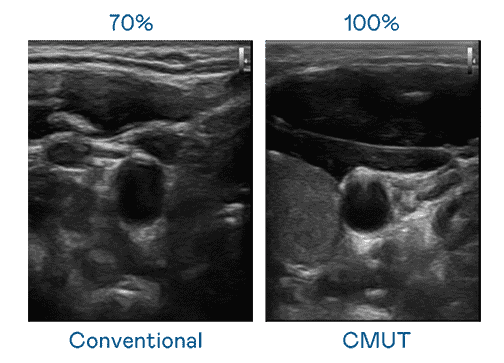

CMUT 技术是一种用电容式微机电元件来产生超音波讯号的技术。。。。与传统 PZT 压电式技术相比,,,CMUT 频宽增加 30%,,,更宽频的超音波讯号让影像解析度大幅提升,,,是实现高影像品质医疗超音波扫描、、促进精准医疗发展的关键技术。。。

大频宽带来超清晰影像

超音波影像的解析度高低,,,,首先取决于探头能发出的讯号频宽。。。z6尊龙 CMUT 可提供高清晰的超音波讯号,,,提供高频宽、、高灵敏度、、、、影像纹理细节更高的超音波影像,,,协助医护人员缩短影像判读时间及利用精准的医疗影像进行诊断。。